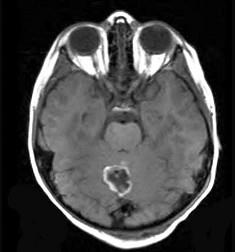

问题 颅内肿瘤(如图所示)好发年龄组是()

选项 A.12~20岁 B.20~30岁 C.20~50岁 D.30~40岁 E.>50岁

答案 C